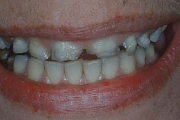

Turritavad ülemised lõikehambad.

Ülemise hambakaare kitsenemine ehk tagumiste hammaste risthambumus.